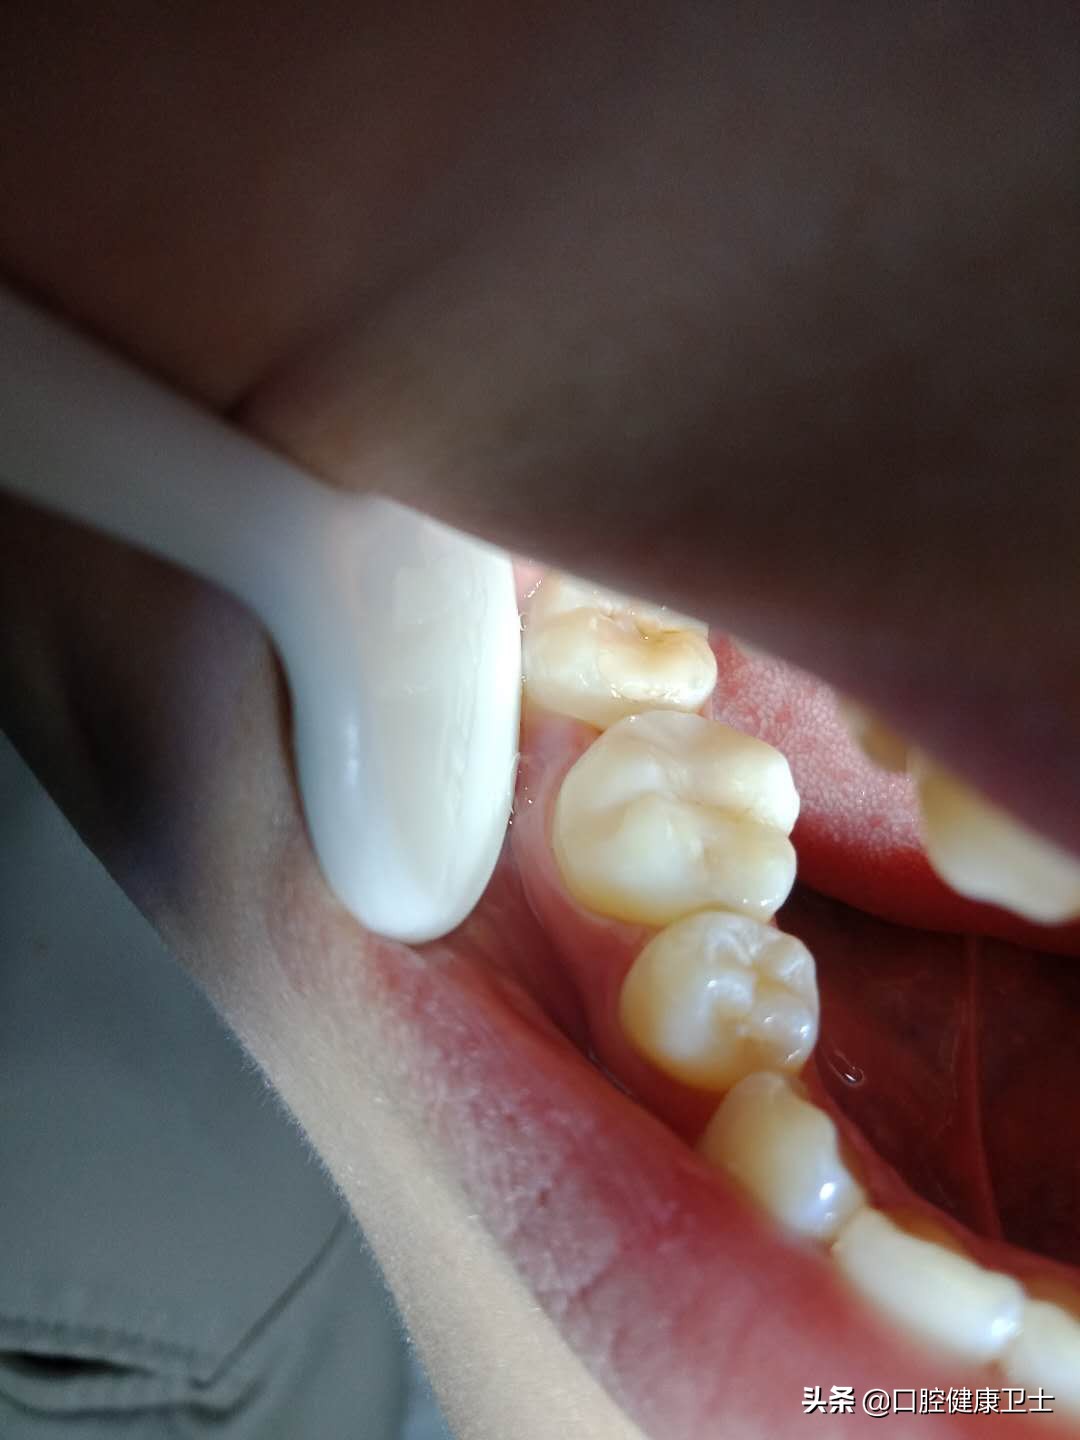

医生:还有问题呢,不仅仅是这些。你看,这张图片更明显,牙齿邻面形态很重要,可你这根本没有把正常邻面形态恢复出来,而是错误的把“牙缝”笼统地堵住了,这就是你出现疼痛的原因。

医生:你看,还有问题呢。看着两张图片,把材料去掉后,牙洞内的腐质都没有去除干净,这是不应该的,以后会出现继发龋,严重的会发展为牙髓炎和根尖周炎,引起剧烈疼痛。

患者:啊!这么黑啊,怎么这么脏。那您帮我清理干净再补吧。